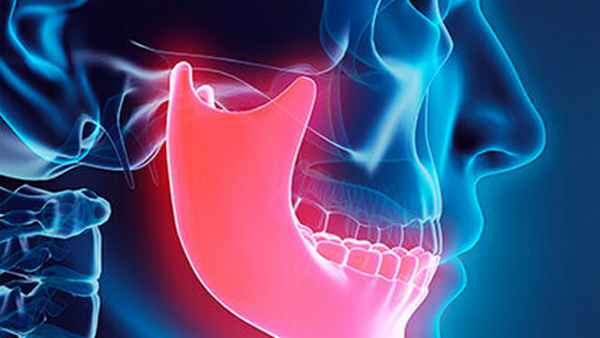

Анкилоз ВНЧС (сокращенно – АВНЧС) – заболевание, проявляющееся снижением или полным отсутствием подвижности нижней челюсти. Патология возникает вследствие фиброзного или костного сращения суставных поверхностей ВНЧС. Зачастую диагностируется в детском и подростковом возрасте, но развивается и у взрослых пациентов вследствие травм и по ряду иных причин. Для профессиональной диагностики анкилоза и эффективного лечения записывайтесь на консультацию в клинику Стоматология 32!

Анкилоз - это костное или фиброзное сращение суставных поверхностей височно-нижнечелюстного сустава, которое приводит к устойчивому, полному или неполному ограничению подвижности нижней челюсти.

При анкилозе ВНЧС, из-за недоразвития нижней челюсти, нередко развивается деформация лица.